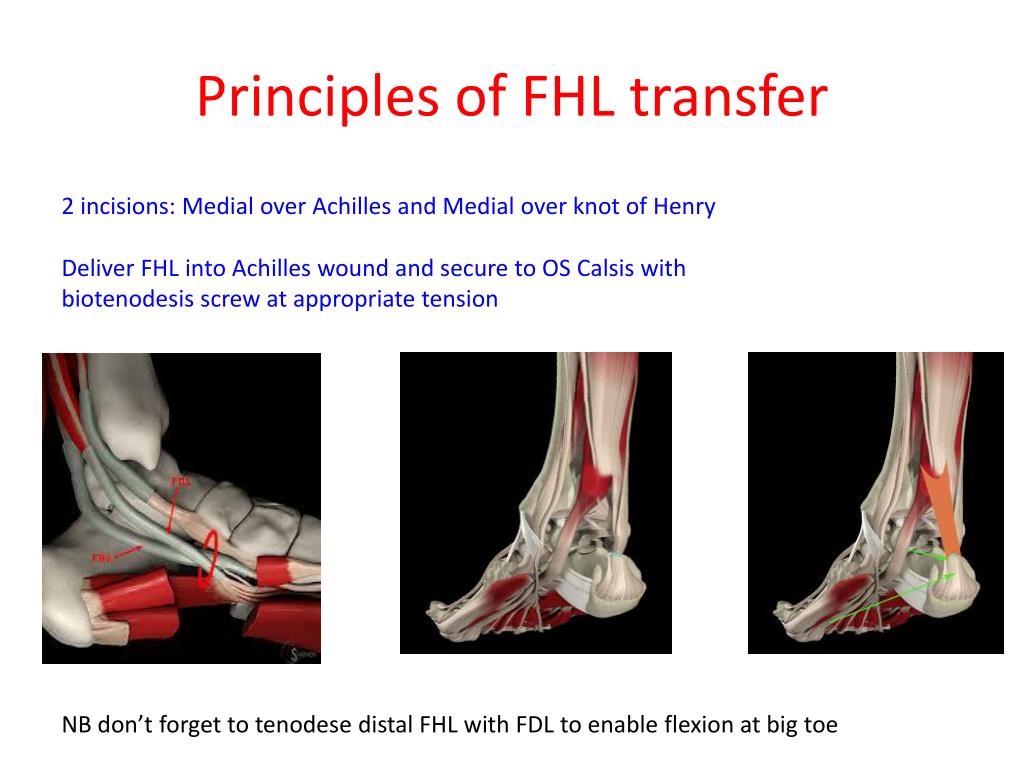

The flexor hallucis longus (FHL) is the muscle and tendon responsible for flexing the big toe. While essential for balance, it is not as critical for walking as the Achilles. In a tendon transfer, the FHL is rerouted from its original path and attached to the calcaneus (heel bone), effectively taking over the role of the missing Achilles tendon.

In this patient’s case, the surgical team employed a dual approach. On one side, an open surgical technique was used, providing the surgeon with a direct view of the anatomy to ensure secure fixation. On the other, an endoscopic approach was utilized. Endoscopic surgery involves using a small camera and specialized tools through tiny incisions, which typically results in less tissue trauma, reduced postoperative pain, and a lower risk of infection.

The goal of this combined approach is to maximize the stability of the transfer while minimizing the overall surgical burden on a patient who is already facing a complex recovery process in both limbs.

The use of the Achilles tendon repair protocols usually focuses on acute injuries. But, the shift toward FHL transfers for chronic cases represents a critical alternative. By utilizing the FHL, surgeons can restore a significant percentage of the original push-off strength, which is the difference between a patient requiring a wheelchair and a patient being able to walk independently.

the integration of endoscopic techniques reflects a broader trend in orthopedic surgery toward “minimally invasive” interventions. Reducing the size of the surgical wound is not just about aesthetics; it reduces the risk of wound dehiscence (opening of the surgical site), which is a known complication in lower-limb surgeries due to poor blood flow in the ankle region.